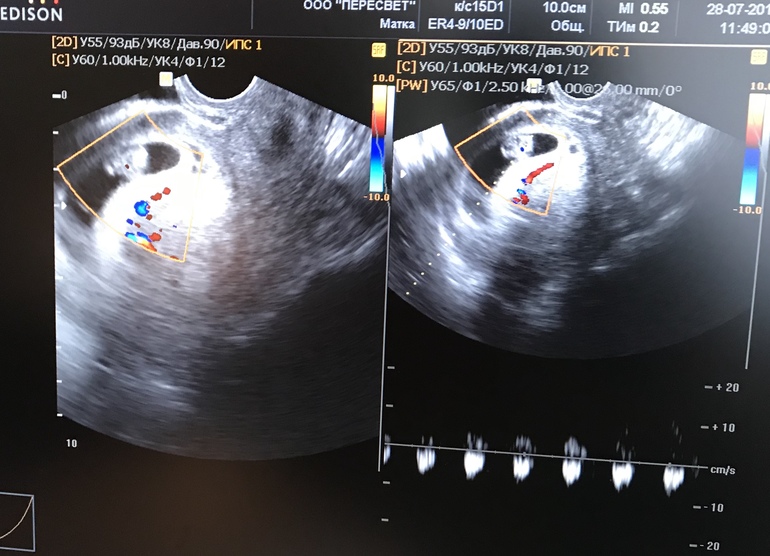

У нас выдают , и самим фоткать разрешают ))) зато первое узи на 7 неделях такое смешное 😂😂😂прям семечка